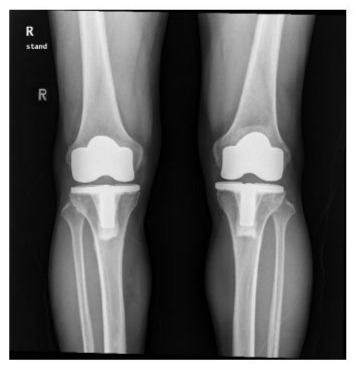

Radiographs of the knees of a 67-year-old woman who had osteoarthritis in both knees (Figure 2A-B).

Figure 2A: Standing anteroposterior radiograph of both knees taken 4 years after surgery, showing that the NexGen LPS-Flex prostheses are embedded solidly in a satisfactory position. There are no radiolucent lines and there is no osteolysis around the components in either knee.

Figure 2B: Lateral radiograph showing that NexGen LPS-Flex prostheses are fixed satisfactorily. There are no radiolucent lines and there is no osteolysis around the components in either knee.

The radiographic results were similar in the NexGen LS-Flex and Freedom TKA groups with regard to the alignment of the knee and the position of the femoral and tibial components in the coronal and sagittal planes. If one assumes a tolerance level of 3°, then the prevalence of outliers ranged from 2 to 4% for all parameters in the NexGen LPS-Flex TKA group and from 1 to 3% in the Freedom TKA group. These differences between the groups were not significant (P > 0.05; Table 4). No knee in either group had osteolysis around the components (Figures 2 and 3).